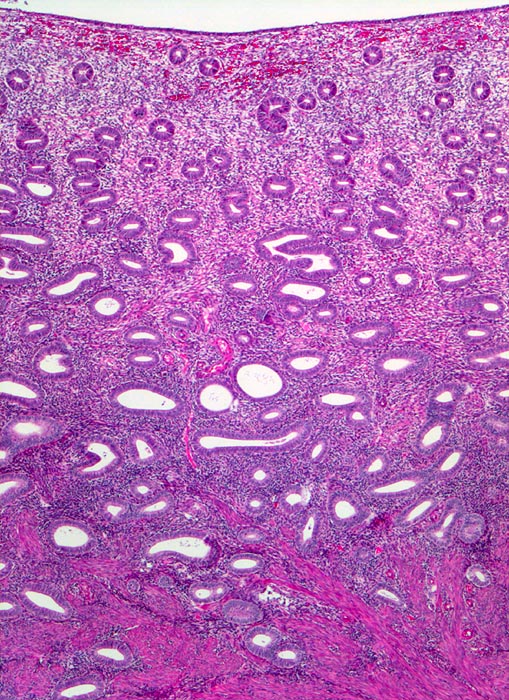

PathoPic – image database / PathoPic ID 3303 - späte Proliferationsphase

späte Proliferationsphase

Endometrium

Hoch aufgebautes Endometrium mit kleinen rundlichen Drüsen und zelldichtem Stroma. Das Endometrium bildet zungenförmige Ausläufer in das darunterliegende Myometrium.

Dysfunktionelle Blutungen bei Uterus myomatosus.